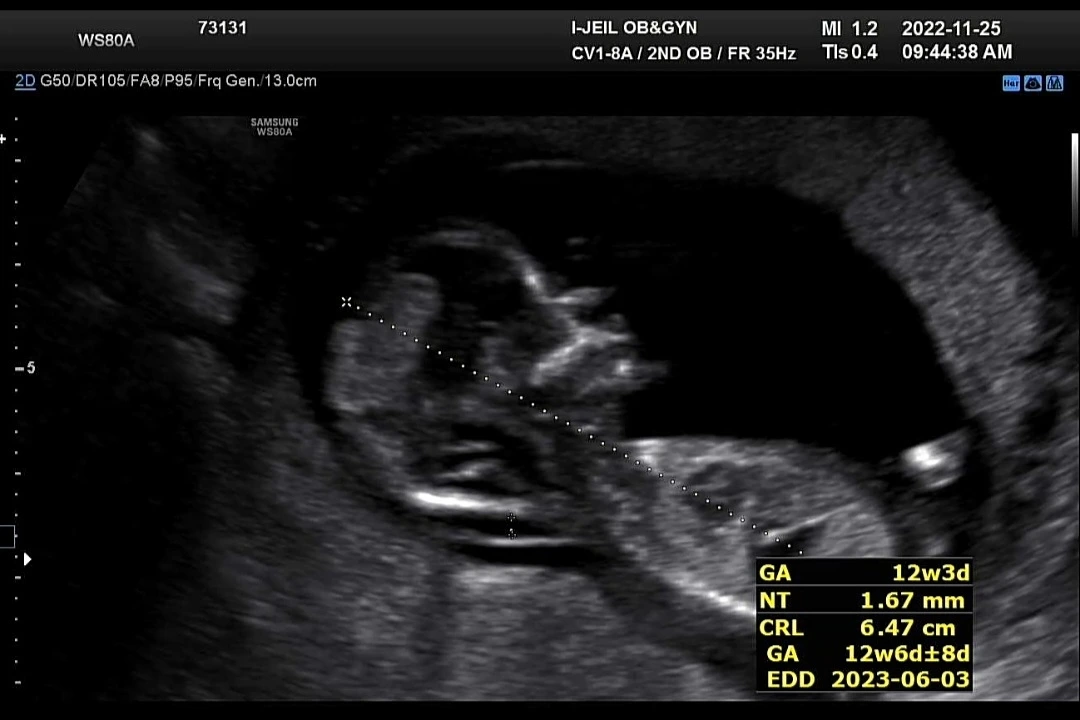

그리고 까꿍이는 드디어 12주 차가 되어 첫 기형아검진을 했다! 너무 긴장되고 떨렸는데 별일이 없으리라고 믿었지만 엄마의 마음이란 게 막상 닥치니 불안해지는 건 어쩔 수 없었다.

1차 검진은 목 뒤 투명대 길이 검사와 콧대 검사를 주로 한다. 목 투명대 검사는 임신 11주~13주에 하는 검사로 태아 목덜미 길이가 보통 3mm 이하여야 정상 범위로 본다.(병원에 따라 2.7mm 이상이면 고위험으로 보기도 한다)

긴장감이 흐르던 10여 분의 초음파 검진 이후 리 까꿍이는 다행히 모두 정상 범위로 나왔다!

목 투명대 길이는 1.5~1.75mm였고 콧대도 정상적으로 확인되었다. 중요 검진 이후 입체 초음파 사진도 한 장 찍어주셨는데 아직은 사람이라기보다는 외계인처럼 보여서 살짝 웃음이 났다.